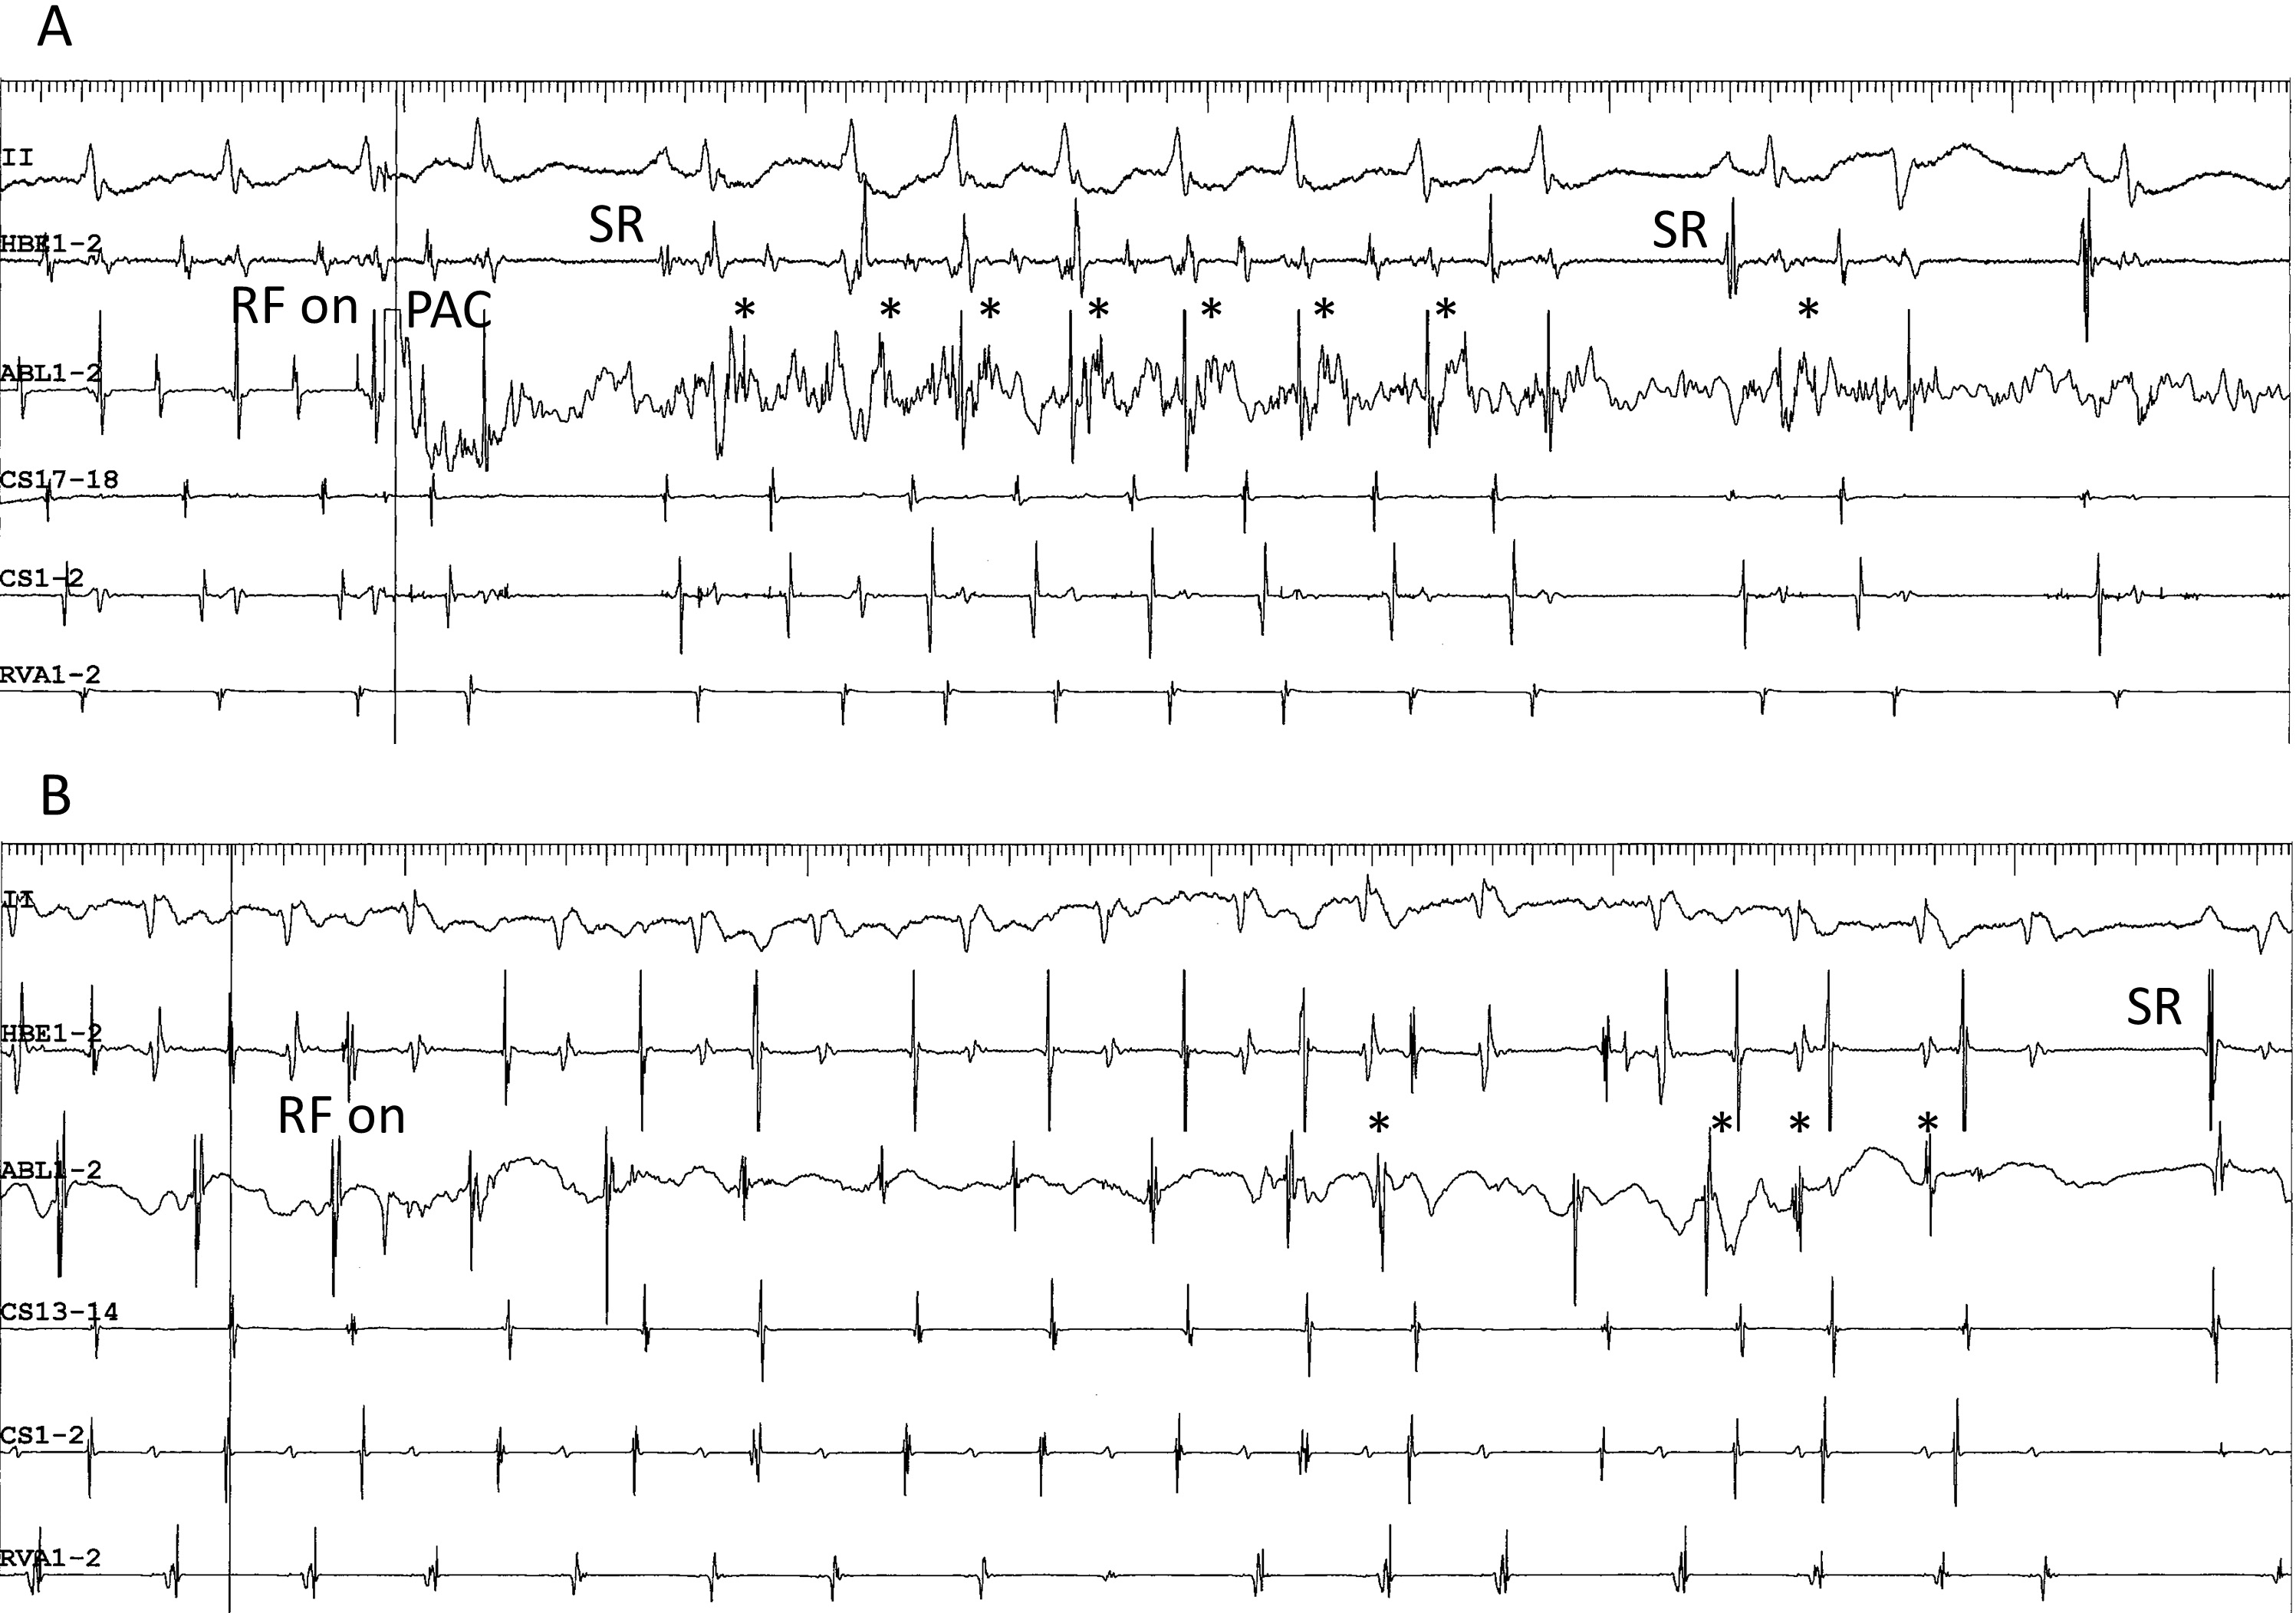

Fig. 4.Representative examples. (A,B) Superior-type of fast-slow AVNRT

successfully ablated in the non-coronary sinus of Valsalva (A) and the right

perihisian region (B). (C) Superoanterior type fast-slow AVNRT. (D) Inferolateral

type fast-slow AVNRT: E: ATP-sensitive atrial tachycardia originating from the

inferolateral right atrial wall, along the tricuspid annulus. Left panels (A) to

(E): intracardiac electrograms during tachycardia at the site of successful

ablation. The asterisks in C, D and E mark the prepotentials preceding the local

atrial electrograms. II, surface electrocardiogram lead II; HBE1-2, His bundle

electrogram; ABL1-2, distal pole of ablation catheter. Middle panels: right (B)

and left (A,C,D,E) anterior oblique fluoroscopic views of the catheter positions

at the site of successful ablation. The white arrow points to the tip of the

ablation catheter. Right panels: left anterior oblique views of three-dimensional

activation maps of the right atrium during tachycardia, using CARTO

Ablation of the superoanterior SP should begin at the site of earliest atrial activation, corresponding to its atrial end (Fig. 4C), as its precise trajectory, especially between its atrial end and the compact AV node, remains unidentified. Each radiofrequency application often causes a shift in the site of earliest atrial activation; therefore, multiple applications may be needed to treat each new site of earliest activation. This phenomenon suggests that the SP widens at its atrial end. More interestingly, low-frequency potentials preceding the local atrial activation are often detectable near the site of earliest atrial activation (Fig. 4C), probably reflecting retrograde activation of the superoanterior SP. These electrophysiological observations contrast with the superior SP, the retrograde activation of which is not always detectable. Intracardiac echocardiography may be useful to navigate the tip of the ablation catheter in the non-coronary sinus of Valsalva [48, 49, 47], the perihisian region [50] or along the tricuspid annulus [51, 52].

The second characteristic is the detection of low-frequency potentials preceding the local atrial activation, near the site of successful ablation. As described earlier, these potentials are found in the superoanterior or inferolateral fast-slow AVNRT (Fig. 4C,D, respectively) and may reflect retrograde activation across the SP [58]. Although the presence of prepotentials during adenosine-sensitive atrial tachycardia has not been reported previously [67, 80, 85], we have reproducibly detected low-frequency prepotentials within a localized area near the site of earliest atrial activation during an atrial tachycardia originating from the inferolateral right atrium, along the tricuspid annulus (Fig. 4E). Yamabe et al. [86] have described low-frequency, late potentials following local atrial activation during sinus rhythm, probably reflecting a delayed activation of the tachycardia origin, near the site of successful ablation, in patients presenting with atrial tachycardia originating from the tricuspid annulus. The presence of these potentials suggests a slowly conducting, common arrhythmogenic substrate of these tachycardias. The third characteristic is the development of accelerated atrial ectopic activity during delivery of radiofrequency energy. This is often observed during ablation of right atrial, superior, superoanterior (Fig. 7A) and inferolateral SP, as described earlier. Moreover, in contrast to previous reports [80, 86], we have also observed it during ablation of atrial tachycardia originating from the tricuspid annulus (Fig. 7B). This activity may be caused by heating of the AV nodal transitional cells present in these tissues [63]. The fourth characteristic is the occurrence of multiple shifts of the site of earliest atrial activation during tachycardia with each radiofrequency application. As described earlier, this phenomenon is occasionally observed after the ablation of superoanterior or inferolateral right atrial SP, or of atrial tachycardia originating from the tricuspid annulus [69]. Collectively, these anatomical, electrophysiological and pharmacological characteristics suggest that the AV node-like tissue distributed around the tricuspid annulus is the arrhythmogenic substrate shared by these tachycardias.

Fig. 7.Development of accelerated ectopic atrial cycles during radiofrequency delivery. (A) Accelerated ectopic atrial rhythm (asterisks) developing immediately after radiofrequency energy was delivered (RF on) during an ongoing superoanterior-type of fast-slow AVNRT, in the same patient as shown in Fig. 4C. The tachycardia is terminated by a premature atrial complex (PAC) immediately after the delivery of radiofrequency energy. (B) ATP-sensitive atrial tachycardia originating from the inferolateral right atrium along the tricuspid annulus, followed by return to sinus rhythm (SR) in the same patient as in Fig. 4E. II, surface electrocardiogram lead II; HRA1-2, high right atrium; HBE1-2, His bundle electrogram; CS13-14 to 1-2, proximal to distal coronary sinus; RVA1-2, right ventricular apex.